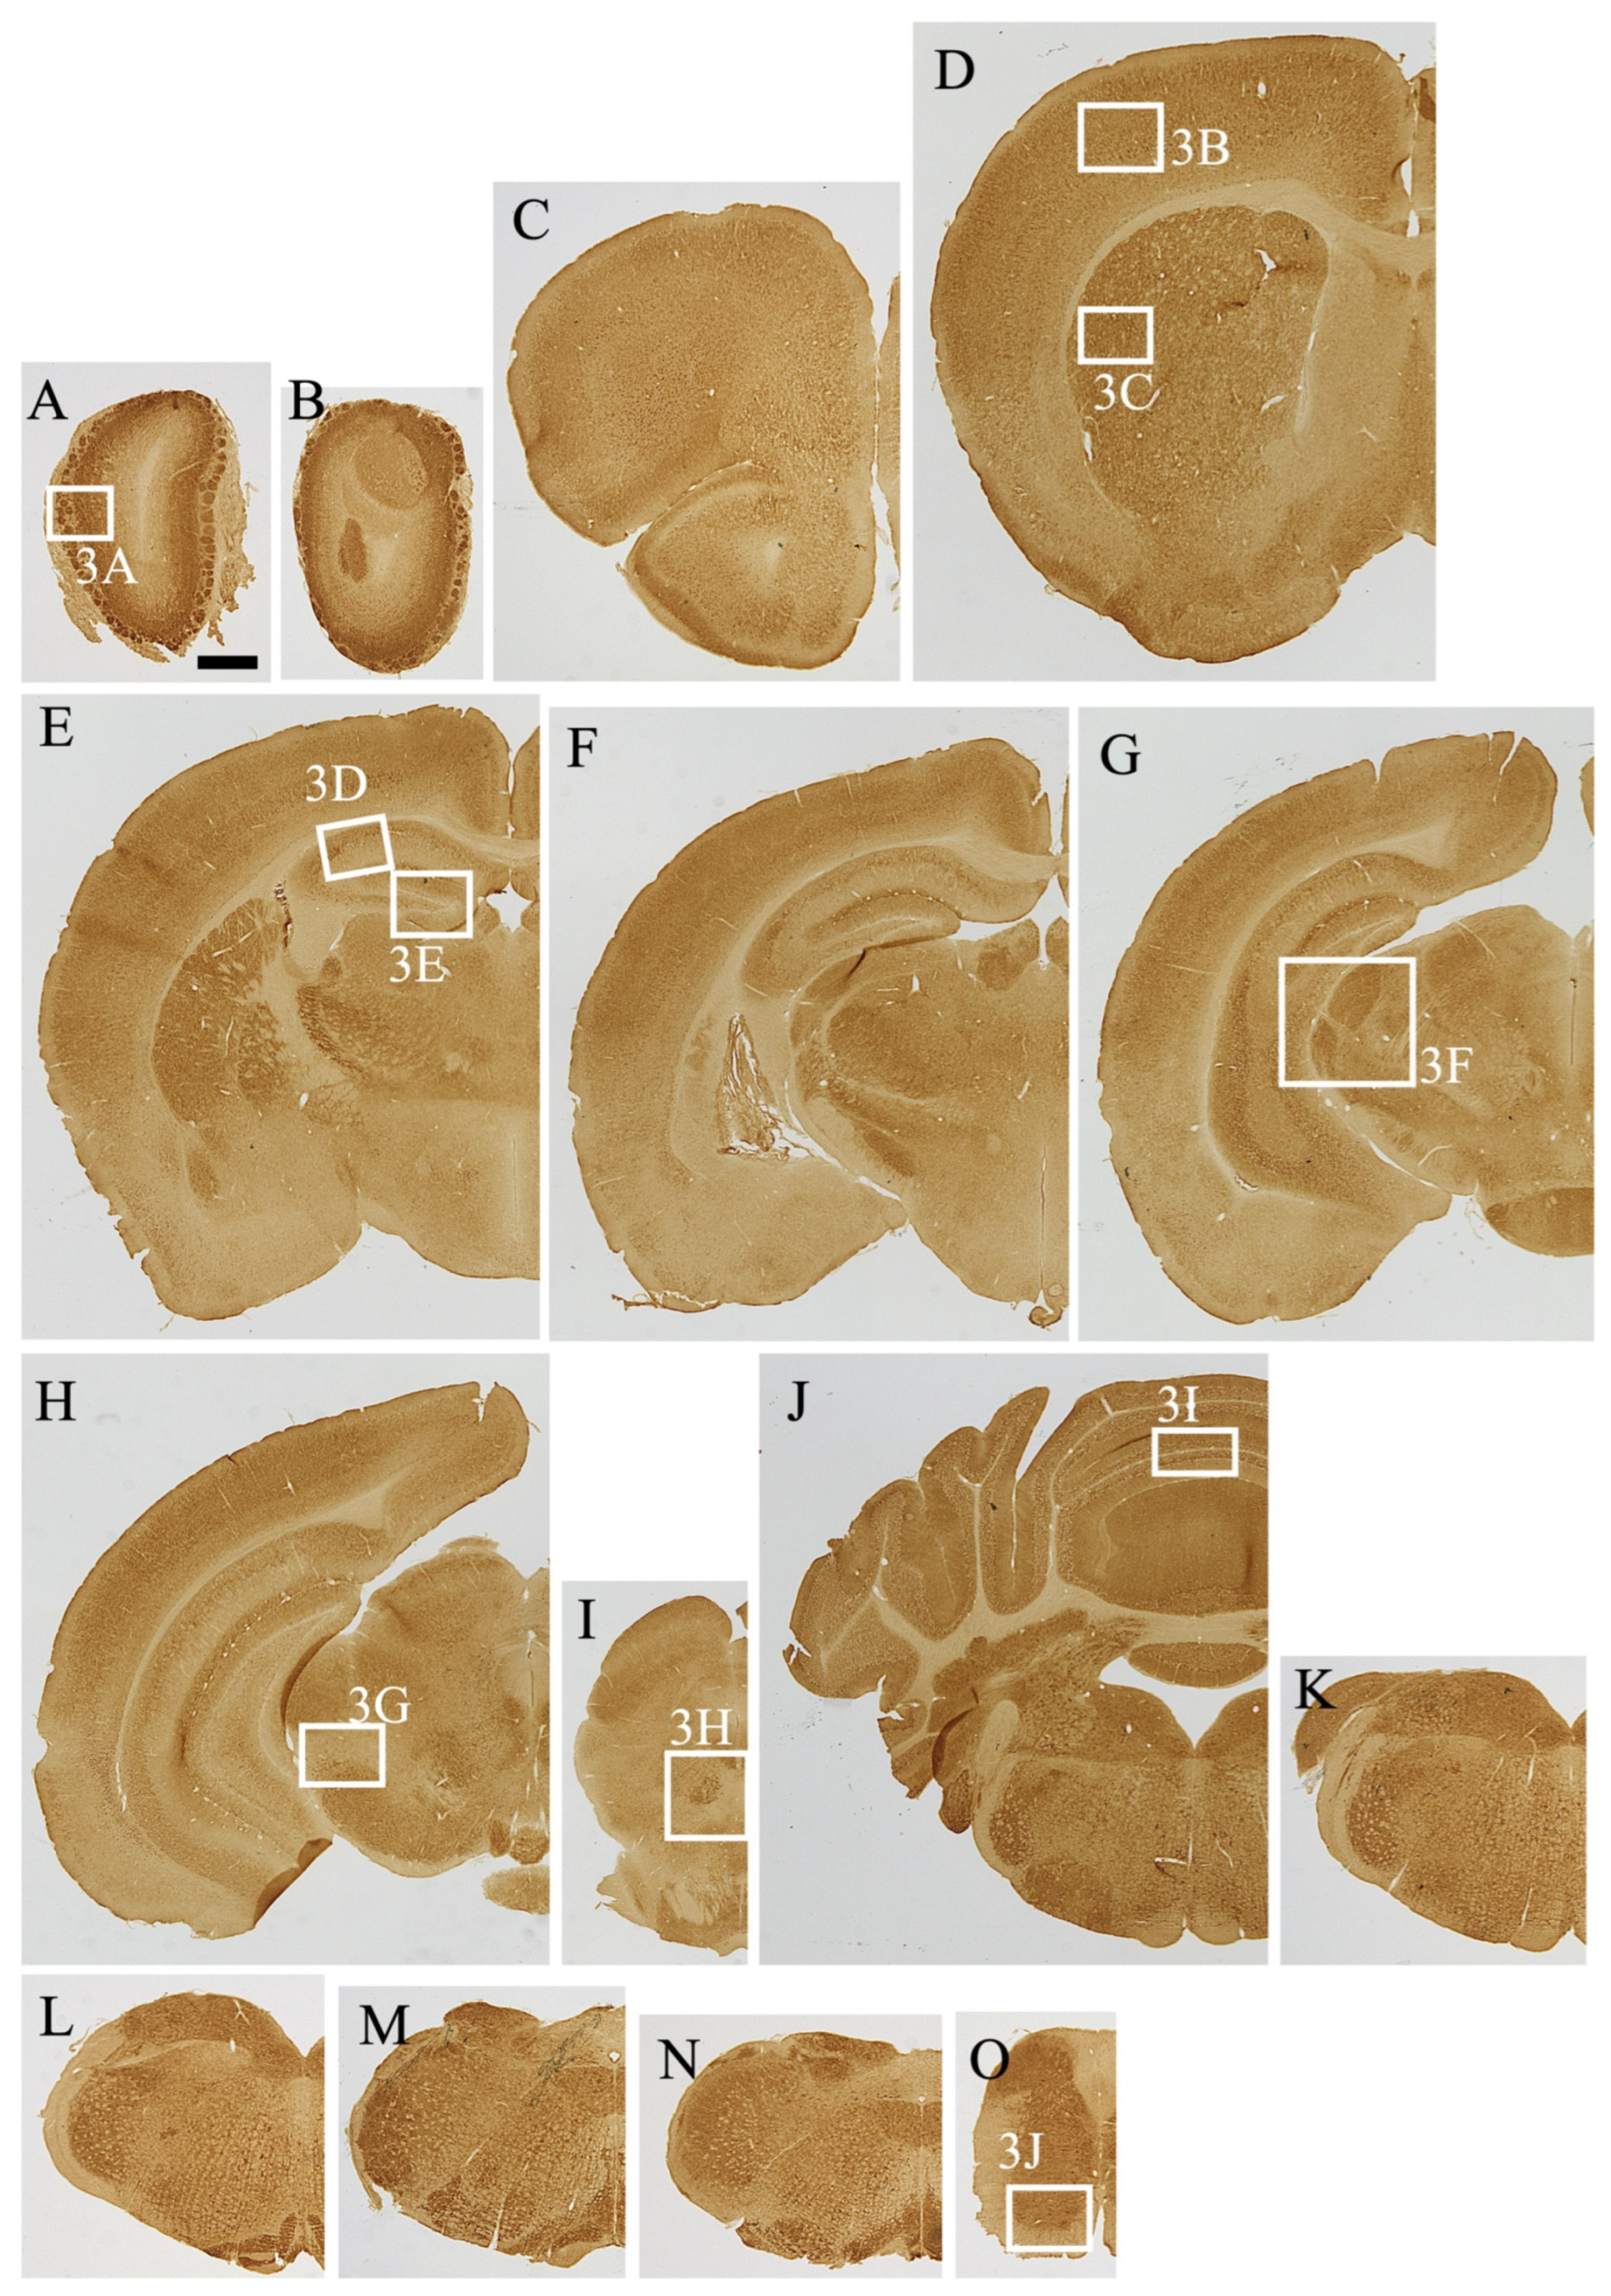

Figure 2.

(A–O) MEGF8 immunoreactivity in the mouse central nervous system in the coronal section along the rostro-caudal axis. White boxes indicate the positions of the high-magnification images shown in Figure 3. Scale bar in (A) = 1 mm.

MEGF8 IR (MEGF8-IR) was mainly observed in the gray matter, which had stronger MEGF8-IR than the white matter. In the gray matter, MEGF8-IR was observed in the neuropils surrounding the soma and neuronal somata.

Hippocampus. Similar to the cerebral cortex, hippocampal cells exhibited layer-specific MEGF8-IR distribution. The CA1–3 pyramidal neuronal somata exhibited low to moderate MEGF8-IR (Figure 2D–G and Figure 3D). MEGF8-IR displayed moderate intensity in the CA1–2 radial and CA3 lucid layers. The dentate gyrus (DG) displayed strong staining, apart from the neuronal layer (Figure 2D–G and Figure 3D). The molecular layers of the DG showed high levels of neuropil staining. In comparison, the polymorphic layer (hilus) exhibited cell-specific and weak to moderate staining in the neuropil. In Ammon’s horn, moderate intensity of MEGF8-IR was observed in the neuropils of the stratum oriensis and stratum radiatum.

(A–J) High-magnification views of MEGF8 immunoreactivity shown in Figure 2. (A) olfactory bulb, (B) cerebral cortex, (C) caudate putamen, (D) Ammon’s horn of the hippocampus, (E) dentate gyrus, (F) dorsal and lateral geniculate nucleus, (G) lateral part of the substantia nigra, (H) dorsal raphe nucleus, (I) cerebellum, and (J) dorsal horn of the spinal cord. Scale bars in (A,I) = 100 μm, (B–G,J) = 200 μm, and (H) = 400 μm.